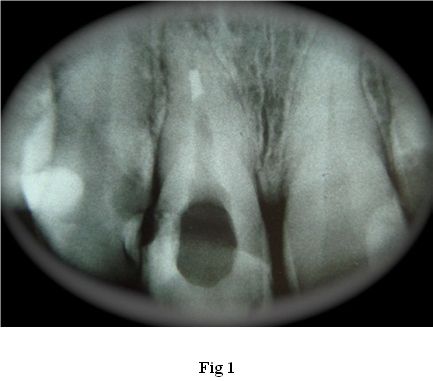

Al estudio RX se aprecia un conducto amplio, sobre todo en su tercio cervical con paredes bastante delgadas. (Fig. 1)